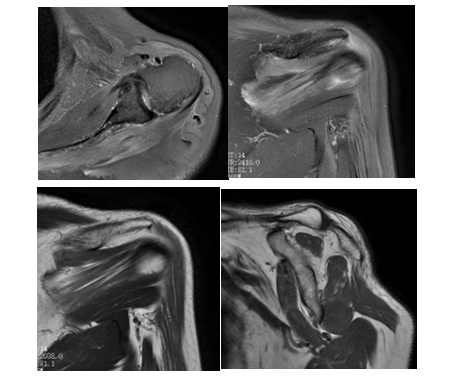

我院核磁检查可见:冈上、下肌、三角肌体积减小,并可见T2WI高信号水肿影,肌束间隙脂肪信号增多。

患者虽然为老年患者,但是经常拳击锻炼,肌肉应该是发达状态,从影像检查来看,肌肉萎缩并水肿,不符合正常人群的表现,随后经多学科会诊,考虑肩袖去神经支配综合征。

影像学特征:肩关节最适合的检查是磁共振,在急性期,显示肌肉水肿,在T2WI上可见高信号影,随后开始产生肌肉萎缩,在T1W可见脂肪浸润。

诊断与鉴别诊断:肩胛上神经受累时累及冈上、下肌;腋神经受累时影响三角肌。结合磁共振检查结果及病人体格检查、临床资料,诊断此病并不难。但是需要与其他疾病鉴别,如废用性肩胛带肌萎缩;四边孔综合征;肩部周围的其他卡压综合征:如肩胛上切迹中的肿块。